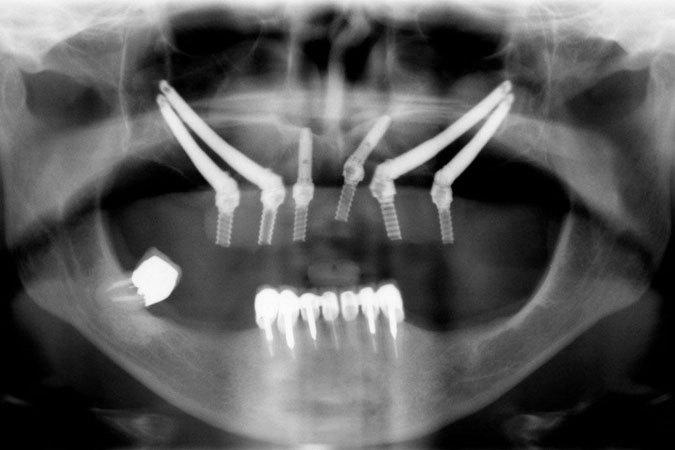

Los implantes cigomáticos son a día de hoy la mejor alternativa al injerto de hueso en el caso de atrofia maxilar.

Los implantes cigomáticos en tan sólo unos días de tratamiento permiten, a quienes no tiene suficiente hueso maxilar, colocar una prótesis fija sustituyendo a las prótesis tradicionales y engorrosas.

El injerto de hueso (implantes convencionales en la foto) es una solución para pacientes sin dientes pero tiene ciertas limitaciones como por ejemplo:

Son implantes que se anclan sobre el hueso cigomático (de allí su nombre). El hueso cigomático se encuentra en los pómulos y es muy resistente, por eso la dentadura permanece bien sujeta y firme con el paso de los años. Es la mejor elección para personas que lleven tiempo sin dientes o que hayan pasado por una fuerte enfermedad periodental.

Además, con implantes cigomáticos se sabe desde el primer momento dónde se pueden poner y qué tipo de prótesis se puede usar. Los implantes cigomáticos no son una solución apta para todas las situaciones en las que falte hueso, pero en los casos que sí se pueda hacer tiene ventajas enormes para el paciente.